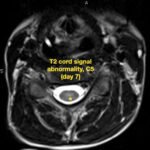

There is a growing body of literature and scientific discovery on pediatric autoimmune encephalitides. This is a heterogenous group of neuroinflammatory conditions leading to often perplexing acute and progressive neurologic and/or neuropsychiatric symptoms. This report demonstrates the evaluation and management of an adolescent with myelin-oligodendrocyte glycoprotein (MOG) antibody-associated fulminant acute disseminated encephalomyelitis (ADEM) in the context of current literature. The featured magnetic resonance imaging uniquely highlights progressive central nervous system lesions detected over the course of the first week of disease.